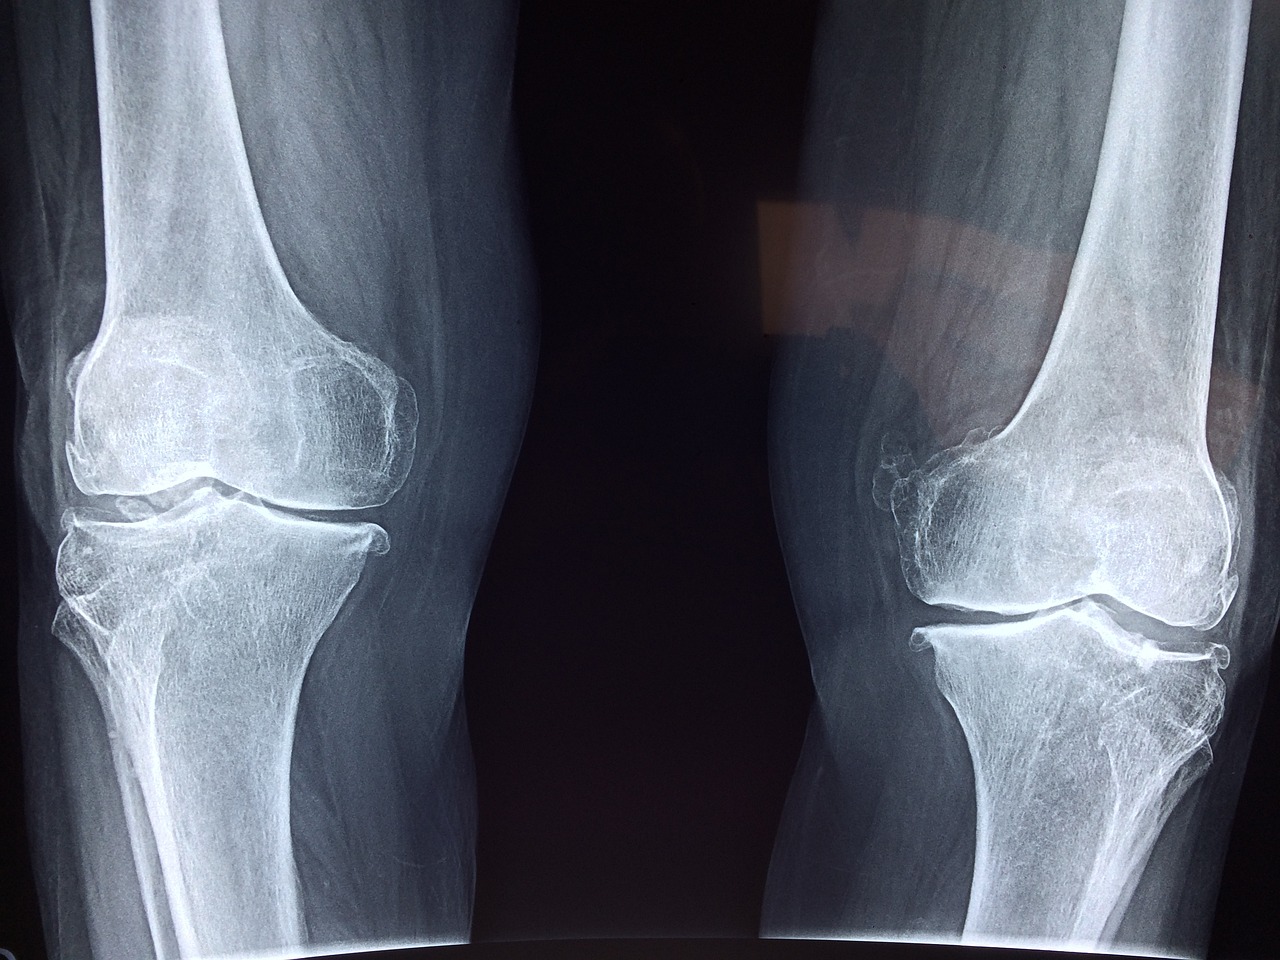

- 골관절염(Osteoarthritis): 연골이 점차적으로 닳아 없어지는 퇴행성 질환으로, 주로 노화나 반복적인 사용으로 인해 발생합니다. 무릎, 엉덩이, 손가락 관절에 주로 발생합니다.

2. 인공 관절 치환술 (Joint Replacement Surgery):

- 손상된 관절을 인공 관절로 교체하는 수술입니다.

- 주로 고관절과 무릎 관절에 시행되며, 심한 관절염 환자에게 유용합니다.